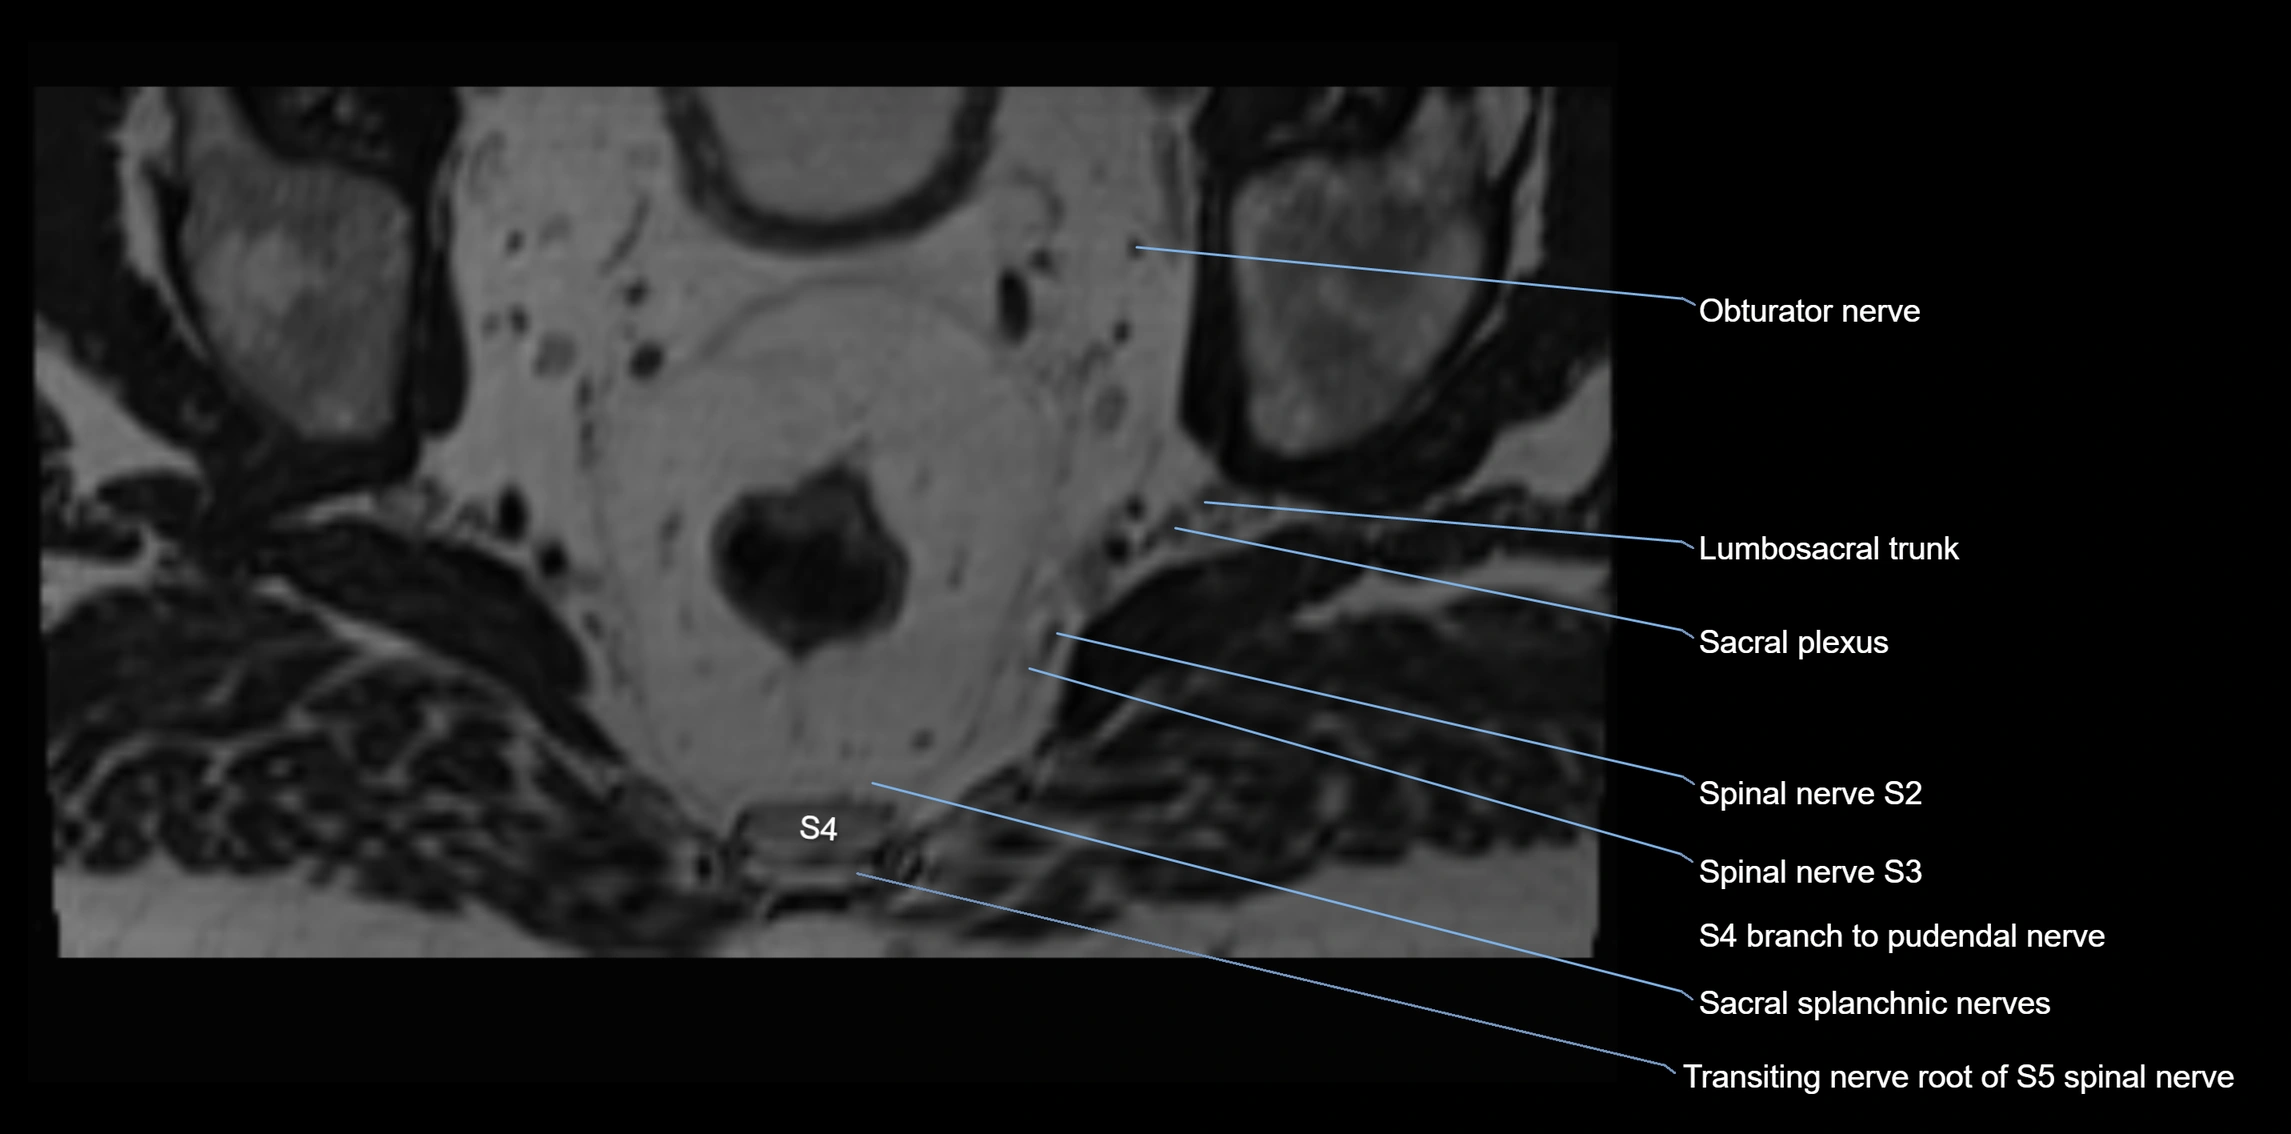

MRI image

image